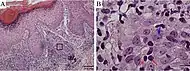

| Mycosis fungoides | Present | Focal | Regular or irregular | Normal | Normal | Minimal or no spongiosis; ±Pautrier microabscess | Atypical lymphoid cells lining the dermo–epidermal junction |  Pautrier microabscesses |